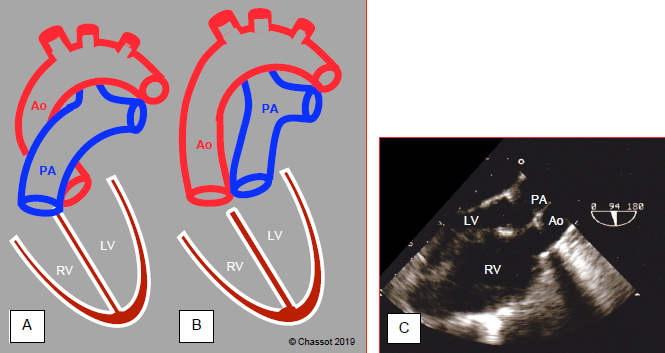

TGA is the most common cyanotic heart disease at birth. It accounts for 5-7% of all congenital heart disease cases and mainly affects boys. TGA entails complete discordance of the ventriculoarterial junction, with the aorta stemming from the anatomically right ventricle acting as the systemic ventricle and the pulmonary artery stemming from the morphologically left ventricle. In dextro-TGA (D-TGA or classic TGA), the two vessels run parallel – the aorta is anterior and the pulmonary artery is posterior. The aortic valve is located in front and to the right of the pulmonary valve (Figure 14.64).

Figure 14.64: Diagram showing transposition of the great arteries (TGA). A: normal position of the aorta and pulmonary artery. B: position of vessels in TGA. C: long-axis view of the aorta and PA, which appear parallel instead of crossing at 45°. The anatomically right ventricle is hypertrophied since it acts as a systemic ventricle (sub-aortic).